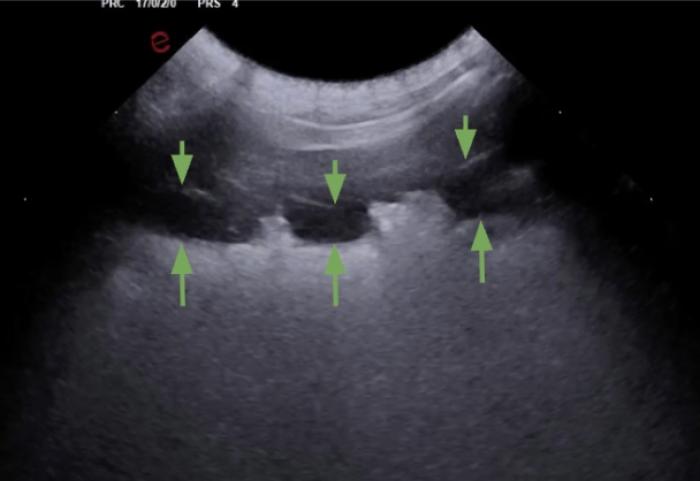

Comenzaremos posicionando el transductor perpendicular a las costillas en uno de los espacios intercostales, pudiendo evaluar al menos el espacio entre dos costillas, la línea PP y no más de 2-3 cm de profundidad de campo (Figura 1A-B).

Son visibles en todo pulmón bien ventilado, pero también estarán presentes en el neumotórax por lo que en este punto es vital observar el deslizamiento de la LP para su diferenciación (Figura 3A-B).